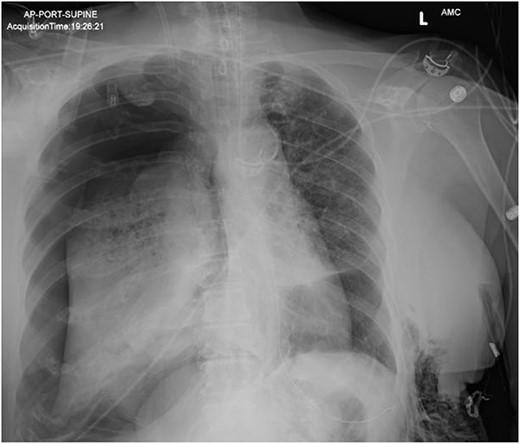

AP upright chest radiograph showing placement of right-sided chest tube and resolution of right pneumothorax.